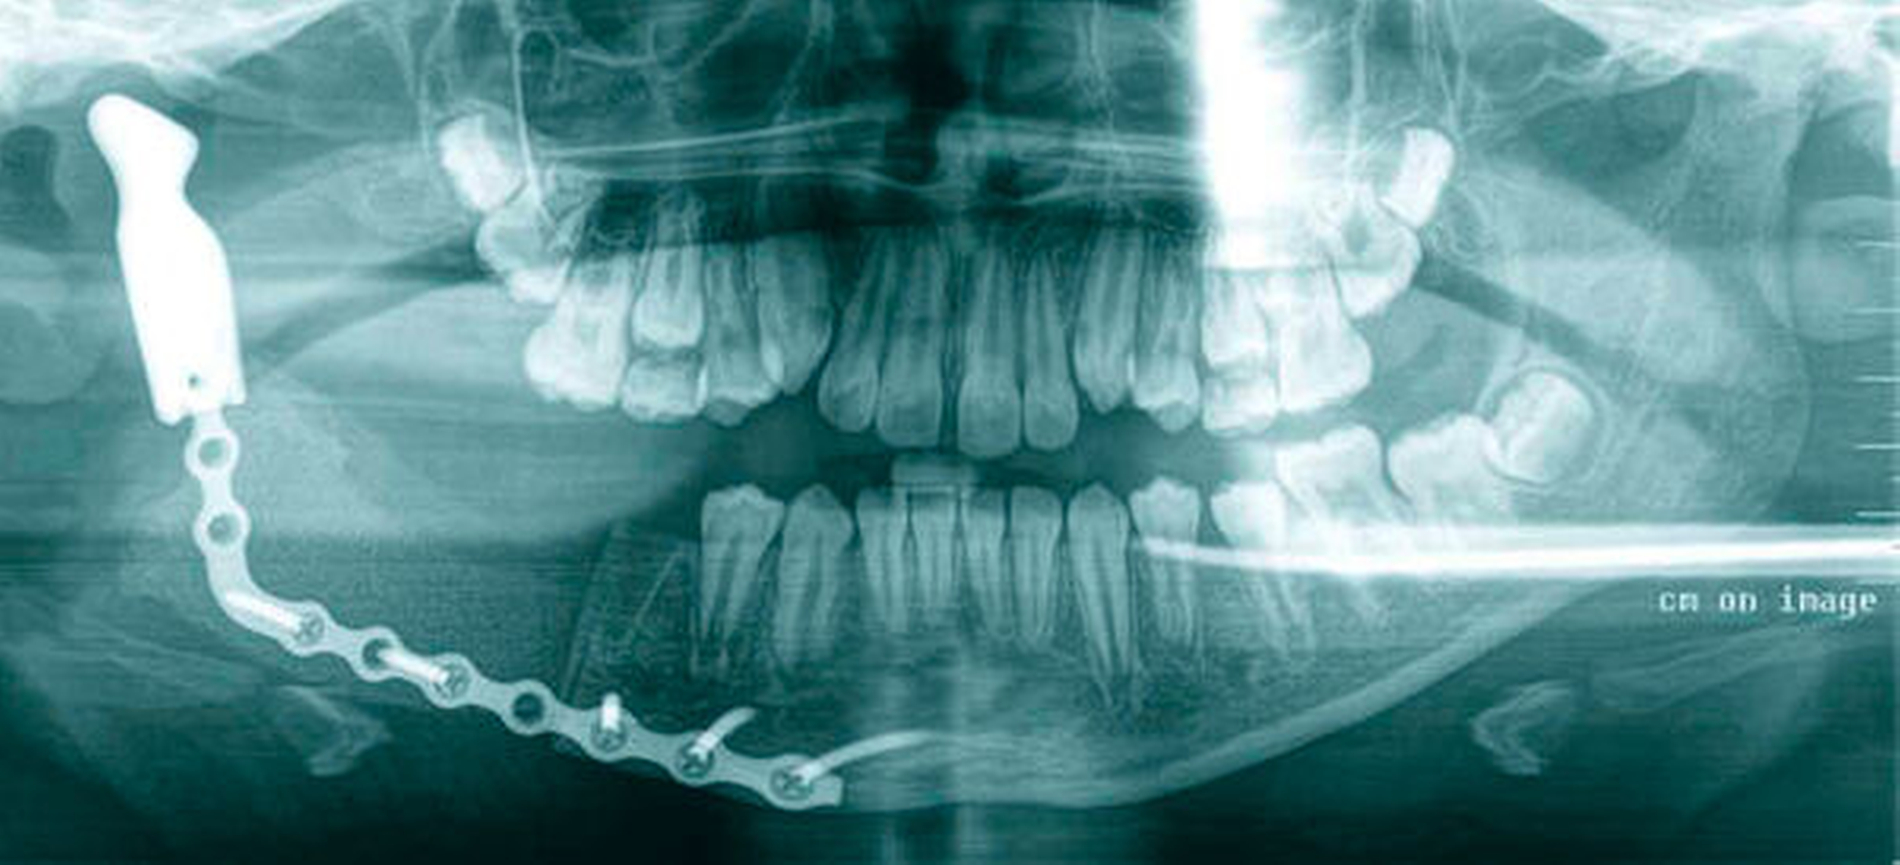

Geplant wurde eine zweizeitige Therapie: Im ersten Schritt erfolgte die Unterkieferteilresektion mit histologisch gesicherter, kompletter Entfernung des Tumors. Dabei wurden sowohl der Nervus alveolaris inferior als auch die Zähne 46 und 45 geopfert. Während des gleichen Eingriffs wurden ein freies Beckenkammtransplantat (60 mm x 25 mm x 15 mm) zur Rekonstruktion des Unterkiefers und ein zur temporären Wiederherstellung des Gelenks an einer Rekonstruktionsplatte befestigtes konfektioniertes Kondylusimplantat eingebracht (Abbildung 3). Schon 14 Tage postoperativ konnte auf Unterarmgehstützen verzichtet werden. Das Gangbild zeigte sich auch im Verlauf normal und ohne Einschränkungen.